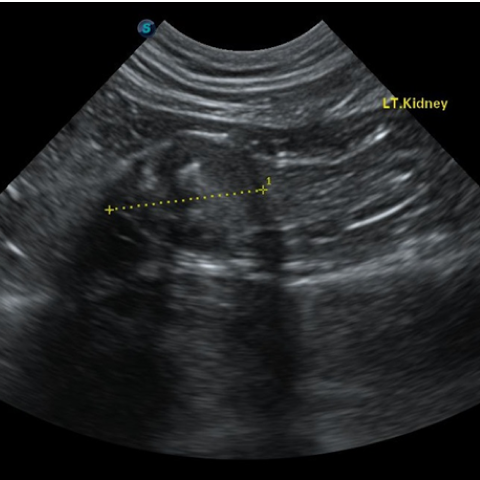

´Ù³¶¼º½ÅÀ庴

(PKD, Polycystic Kidney Disease)(Triaditis)

´Ù³¶¼º½ÅÀ庴À̶õ, ½ÅÀå¿¡ ´Ù¼öÀÇ ³¶Á¾ÀÌ ¹ß»ýÇϰí ÀÌ·Î ÀÎÇØ ½ÅÀå ±â´ÉÀÌ ÀúÇϵǸ鼭 ¼­¼­È÷ ¸¸¼º ½ÅºÎÀüÀ¸·Î ÁøÇàµÇ´Â ÁúȯÀÔ´Ï´Ù. ÁÖ·Î Æä¸£½Ã¾È, È÷¸»¶ó¾á °°Àº ´ÜµÎÁ¾ °í¾çÀ̵鿡°Ô¼­ ³ªÅ¸³ª´Â À¯Àüº´ÀÇ ÇϳªÀ̸ç, ´Ù³¶¼º½ÅÀåÀ» °¡Áø °í¾çÀ̵éÀº Æò±Õ 4¼¼¿¡ ÀÌ¹Ì ½ÅÀå ±â´ÉÀÌ ¼Õ»óµÇ±â ½ÃÀÛÇÑ´Ù°í º¸°íµÇ°í ÀÖ½À´Ï´Ù. µû¶ó¼­ ÀÌ·¯ÇÑ Á¾·ùÀÇ °í¾çÀ̵éÀÇ °æ¿ì ºñ±³Àû ¾î¸° ¿¬·ÉºÎÅÍ Áö¼ÓÀûÀ¸·Î ½ÅÀå ±â´ÉÀ» ¸ð´ÏÅ͸µ ÇÏ´Â °ÍÀÌ ÇÊ¿äÇÕ´Ï´Ù. ¶ÇÇÑ ½ÅÀå »Ó ¾Æ´Ï¶ó ÁÖº¯ Àå±âÀÎ ºñÀå, °£, ÃéÀå¿¡µµ ³¶Á¾ÀÌ »ý±â¸é¼­ À̵é Àå±âµµ ¹®Á¦°¡ µÉ ¼ö ÀÖÀ¸¹Ç·Î Á¤±âÀûÀÎ °Ç°­°ËÁøÀ» ÅëÇØ °í¾çÀÌÀÇ °Ç°­ »óŸ¦ È®ÀÎÇÏ´Â °ÍÀÌ ÁÁ½À´Ï´Ù.